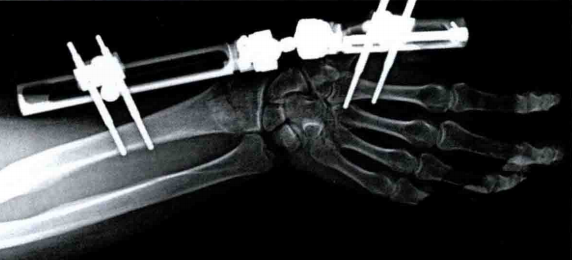

2、手术治疗

手术目的:

恢复关节面的平整及相邻关节面的吻合关系,重建关节的稳定性以及恢复无痛且功能良好的腕关节。

手术指征:

• 开放性骨折;

• 骨折合并间室综合征;

• 合并神经血管或(和)肌腱损伤;

• 双侧骨折;

• 桡腕关节骨折脱位;

• 关节面的压缩性骨折;

• 掌侧和背侧剪力骨折;

• 掌侧弯曲力骨折;

• 背侧弯曲力骨折,复位后再移位且对功能要求高的患者;

• 手法复位后桡骨短缩超过 3 mm;

• 侧位 X 线片示背侧成角超过 10°;

• 关节面台阶超过 2 mm;

• 手法复位不满意者可采用手术治疗。

手术方法可根据骨折的具体情况选择,包括经皮撬拨复位克氏针内固定、外固定支架固定、切开复位钢板内固定等。